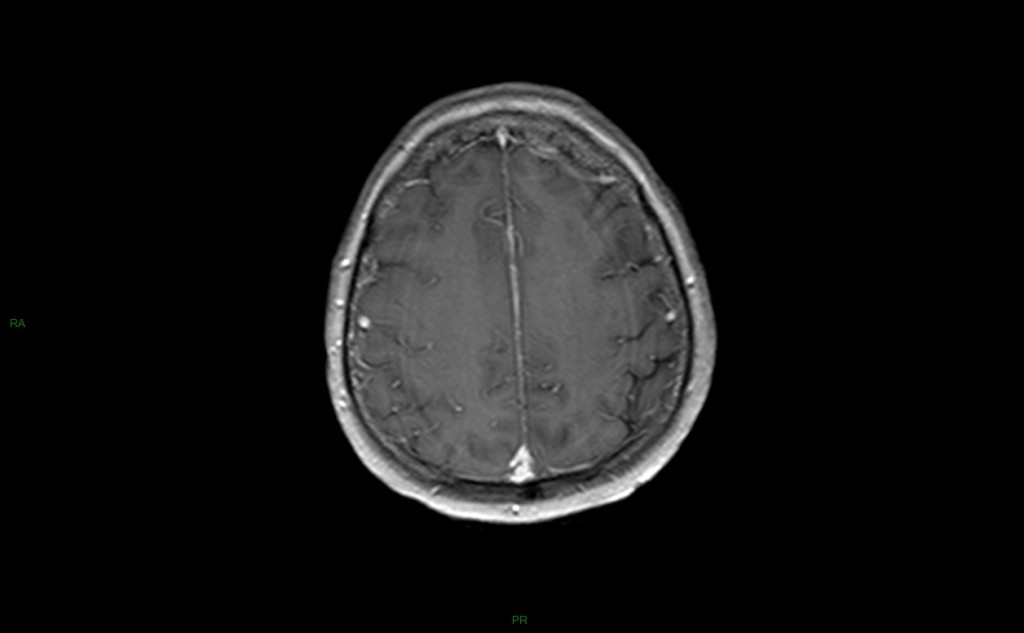

méningo Encéphalite herpétique

• Virus herpex simplex (HSV1)

• 10 à 20 % des encéphalites virales

• Réactivation d’un virus latent du gg trigéminal (de Gasser)

• Syndrome confusionnel fébrile

• Atteinte temporo-limbique

• Ponction lombaire : type lymphocytaire, hyper-protéïnorachie modérée, PCR (ADN viral)

• EEG : focalisation temporale+++

• Mortelle dans 70% des cas si pas traitée

• IRM

• Localisation temporale, temporo-lymbique (cingulum)

• SB et/ou SG

• Epaissisement des gyri, peu d’effet de masse

• Pas de systématisation artérielle

• HypoT1, hyperT2-FLAIR, hyperDiff, ADC variable

• Réhaussement gyriforme après IV

• +++ Respect du putamen +++ (DD avec tumeur)

• Risque : bilatéralisation

• Traitement : anti-viral spécifique précoce

• DD : oligodendrogliome, post critique, encéphalite lymbique, autre encéphalite virale, MCJ

• Évolution : nécrose laminaire